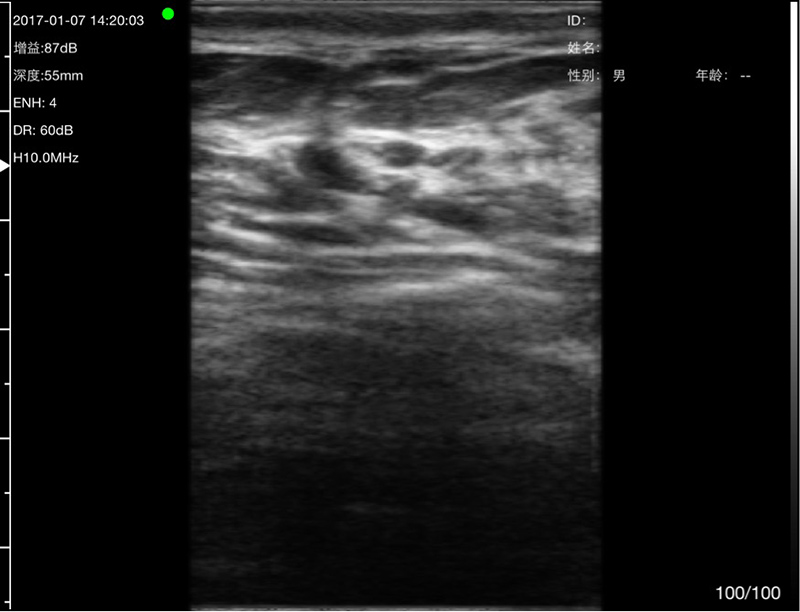

• 探头频率:微凸5.0/7.0MHz,线阵7.5/10 MHz

• 扫描深度:微凸60/90/120/160mm,线阵 20/40/60/80mm,可调

• 显示模式:B、B/M、Color、PW、PDI

• 穿刺辅助功能:平面内穿刺引导线功能,平面外穿刺引导与血管自动测量功能,针尖显影增强功能